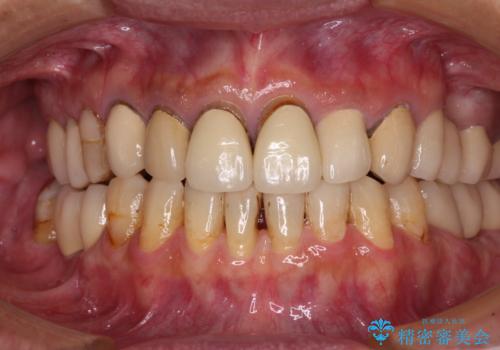

[ インプラント治療 ]失った奥歯を回復したい

![[ インプラント治療 ]失った奥歯を回復したいの症例 治療後](https://seimitsushinbi.jp/wp/wp-content/uploads/2021/11/7d51b0ec04f819febabdd26c9bfb7954-500x350.jpg?v=1637928867)